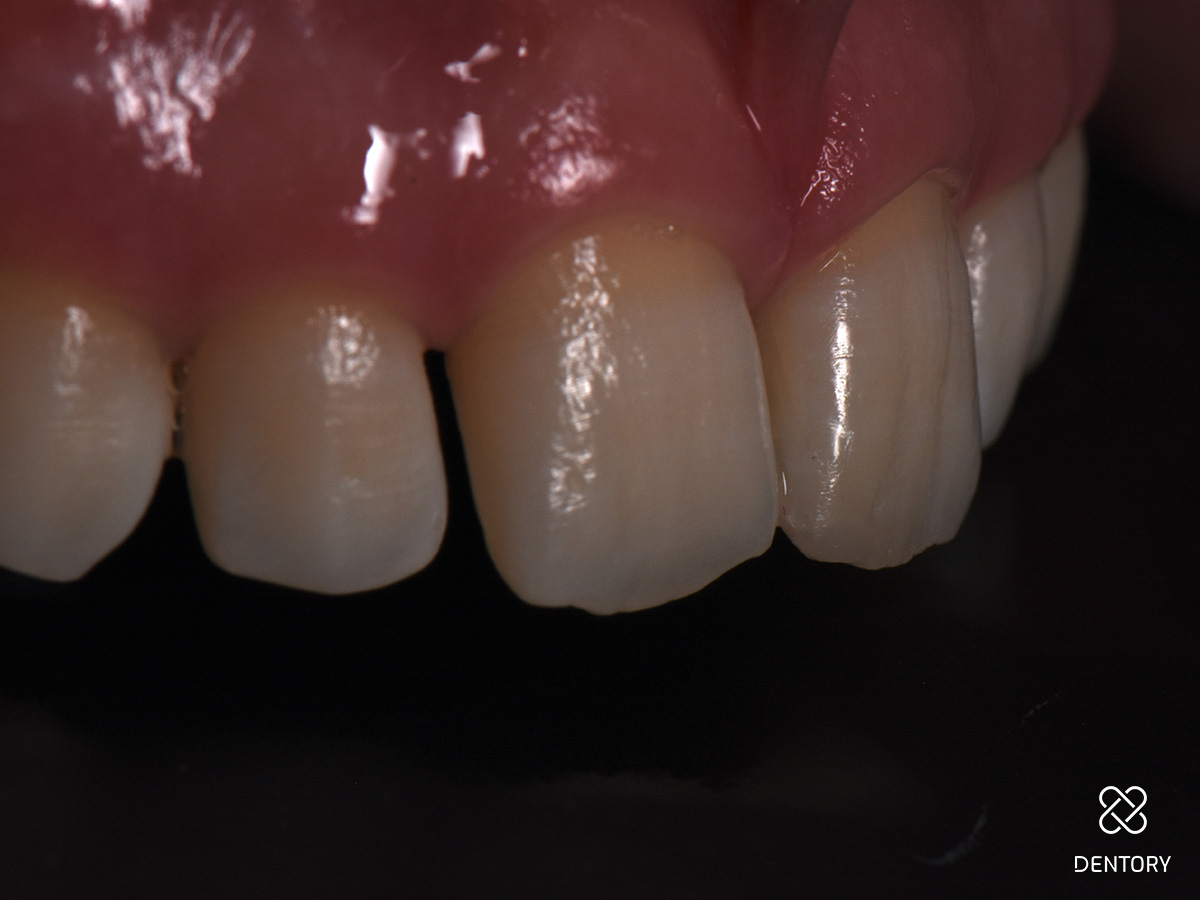

Die Füllung hat sich harmonisch in die Umgebung integriert. Trotz der minimalistischen Gestaltung hat sich ein dezenter Halo-Effekt ergeben.

Abbildung 12

Kontrolle nach 14 Tagen Kleine Füllungsrestaurationen im Frontzahnbereich können sich aufgrund vielfältiger Effekte besonders im Inzisalkanten-Bereich als schwierig erweisen. Dieser Fall zeigt aber, dass bei einer korrekten Farbauswahl sowie Form- und Texturgebung auch ohne komplizierte Methoden zuverlässige Ergebnisse erzielt werden können.